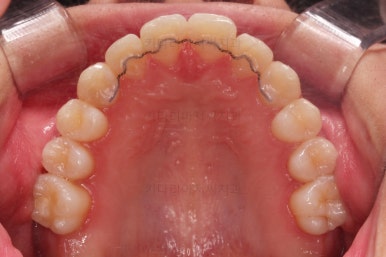

우측 상단에 보이던 어금니도 바로 세운 뒤, 치료를 했습니다.(골드 인레이)

왼쪽 상단으로 보이던 치아도 치료를 했어요.

좌우의 치아가 재료가 차이가 나는데 한 쪽은 튼튼하고 오래 쓸 수 있고, 광범위한 부위에 맞는 인레이라는 치료방법이고요.

왼쪽 치아도 인레이가 추천되는 상황이었지만 경제적인 사정을 고려해서 일단은 건강보험이 적용되는 재료인 GI(지아이)라는 재료로 치료를 했어요.

성질이 약한 단점이 있어서 주기적인 체크가 굉장히 중요합니다.

기타 부위들의 디테일을 좀 더 맞춰주고 치료를 종료합니다.

전후사진을 비교해볼게요.

약간의 주걱턱, 돌출입은 고칠 의사가 없어서 그대로 유지하였고 주걱턱 패턴으로 인한 부정교합 부분을 개선했으며 무엇보다 중요한 것은 쓰러져서 많이 썩어있던 치아를 자칫 치료 못할 뻔 했는데 교정치료와 병행하여 훌륭하게 치료하여 살려 썼다는 점이었어요.